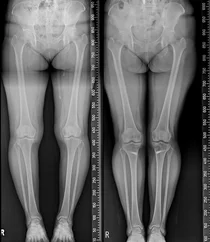

휜다리는 무릎의 건강상태와 걸음걸이, 생활습관, 연령에 따라 ▲내반슬 ▲외반슬 ▲반장슬 등으로 구분되며, 좌식생활이 익숙한 한국인에게는 서 있을 때 양 무릎이 닿지 않고 벌어져 있어 다리가 밖으로 휘어져 있는...